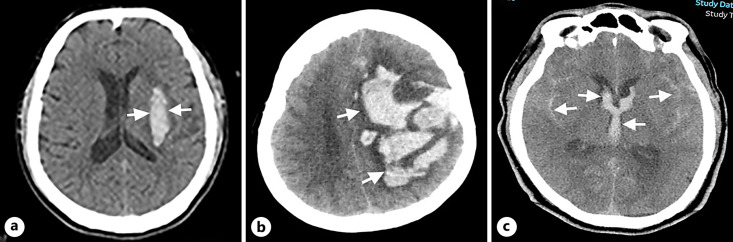

Summary: ICH accounts for approximately 10-20% of all strokes. The incidence of ICH is higher in low- and middle-income than high-income countries and is estimated 8-15% in western countries like USA, UK, and Australia, and 18-24% in Japan, Taiwan, and Korea. The ICH incidence increases exponentially with age, and old age especially over 80 years is a major predictor of mortality independent of ICH severity. Females are older at the onset of ICH and have higher clinical severity than males. Modifiable risk factors include blood pressure, smoking, alcohol consumption, lipid profiles, use of anticoagulants, antiplatelet agents, and sympathomimetic drugs. Non-modifiable risk factors constitute old age, male gender, Asian ethnicity, cerebral amyloid angiopathy, cerebral microbleed, and chronic kidney disease. Blood pressure is the most important risk factor of ICH. Imaging markers may help predict ICH outcome, which include black hole sign, blend sign, iodine sign, island sign, leakage sign, satellite sign, spot sign, spot-tail sign, swirl sign, and hypodensities. ICH prognostic scoring system such as ICH scoring system and ICH grading scale scoring system in Chinese and Osaka prognostic score and Naples prognostic score has been used to predict ICH outcome. Early minimally invasive removal of ICH can be recommended for lobar ICH of 30-80 mL within 24 h after onset. Decompressive craniectomy without clot evacuation might benefit ICH patients aged 18-75 years with 30-100 mL at basal ganglia or thalamus. However, clinical studies are needed to investigate the effect of surgery on patients with smaller or larger ICH, ICH in non-lobar locations, and for older patients or patients with preexisting disability. Surgical treatment is usually associated with neurological sequels if survived. For medical treatment, blood pressure lowering should be careful titrated to secure continuous smooth and sustained control and avoid peaks and large variability in systolic blood pressure. Stroke and cancer are the most common causes of death in Asian ICH patients, compared to stroke and cardiac disease in non-Asian patients.